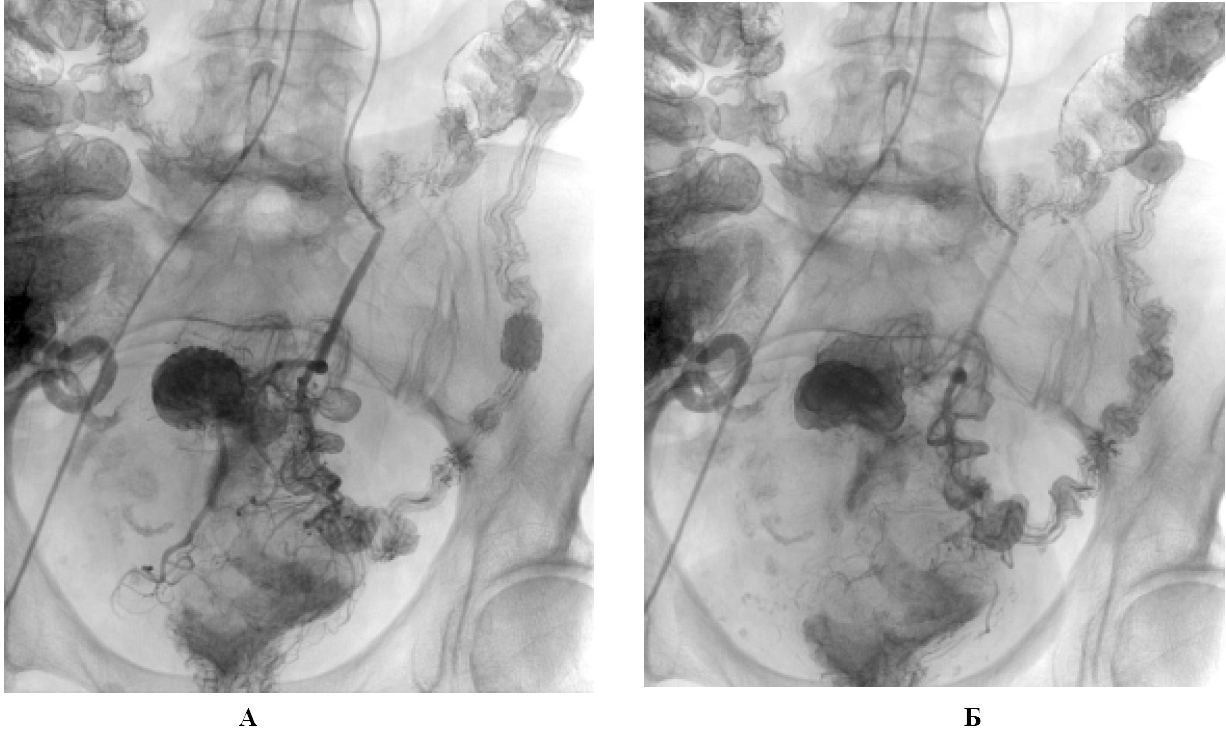

Несмотря на проводимую гемостатическую терапию, 22.02.2013 г. развился рецидив кровотечения — из прямой кишки одномоментно выделились до 150 мл алой крови. С гемостатической целью, а также для проведения предоперационной регионарной химиотерапии 22.02.2013 г. под местной анестезией доступом через правую общую бедренную артерию выполнены артериография нижней брыжеечной артерии, селективная катетеризация и химиоэмболизация верхней прямокишечной артерии (рис. 1).

Рис. 1. Ангиограмма нижней брыжеечной и верхней прямокишечной артерий больной З., 68 лет: А — до эмболизации; Б — после эмболизации верхней прямокишечной артерии

В просвет сосуда ввели суспензию химиопрепарата (оксалиплатин 75 мг) в масляном контрастном препарате (сверхжидкий липиодол 8 мл). Послеоперационный период протекал без осложнений, рецидивов кровотечения из опухоли прямой кишки не было. Через 3-е сут после химиоэмболизации 25.02.2013 г. в плановом порядке выполнена операция: комбинированная передняя аппаратная резекция прямой кишки, экстирпация матки с придатками, холецистэктомия.